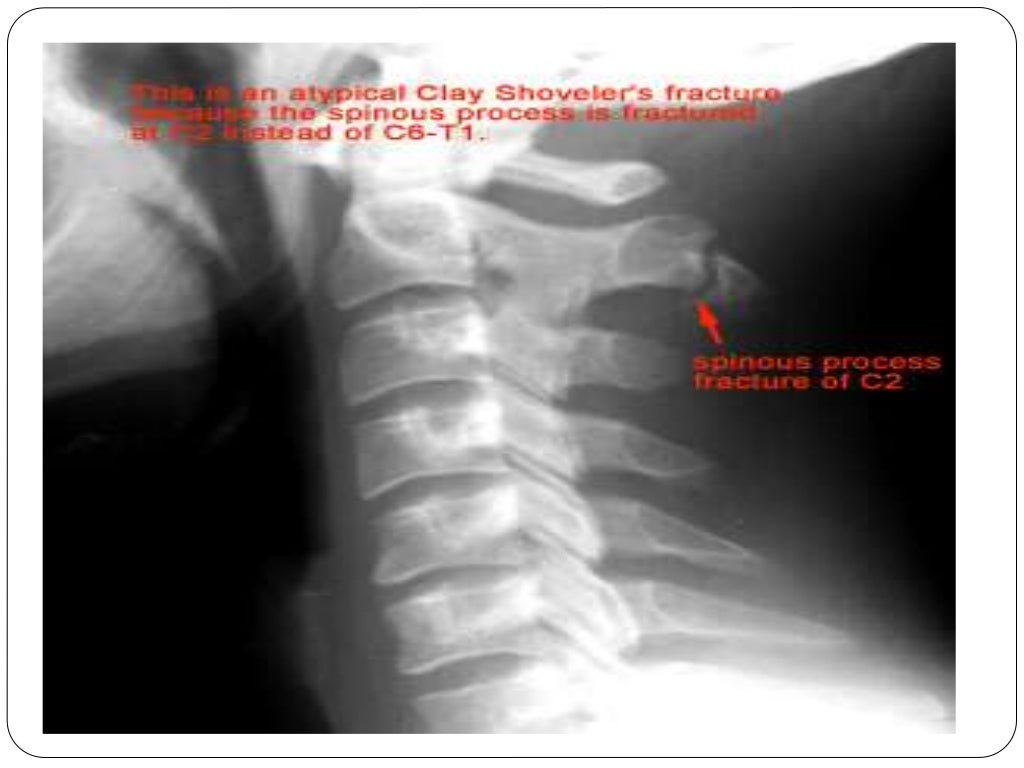

Fracture types Plaster Of Paris tecniques and Complications